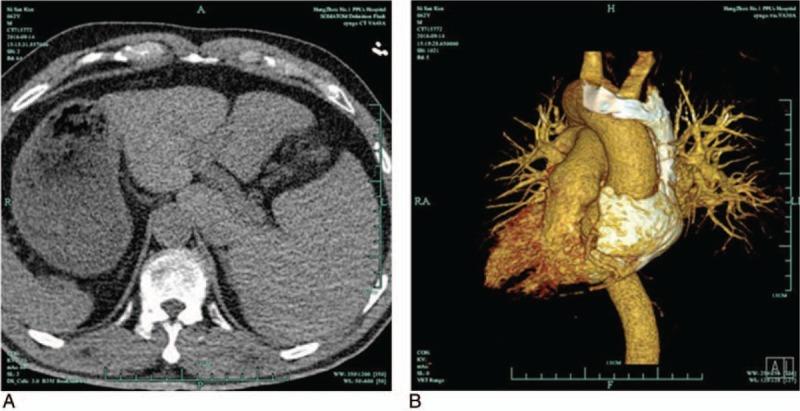

A 62-year-old male with dextrocardia and situs inversus underwent catheter ablation of frequent PVCs. The electrocardiograms (ECG) were recorded by placement of the electrodes in reversed positions. The PVCs exhibited left bundle branch block and inferior axis QRS morphology with transition at leads V2-V3. The activation mapping indicated the earliest site of ventricular activation between the left and right aortic sinus cusps, highlighting that catheter ablation was successful at this point.

The catheter ablation was successful between the left and right aortic sinus cusps, and the PVCs were not detected for the subsequent 30 min following the procedure as well as for the rest of the hospital stay.

一名62岁右位心且内脏反位的男性接受了频繁室性早搏的导管消融。心电图(ECG)通过将电极置于反向位置进行记录。室性早搏表现为左束支传导阻滞和下轴QRS形态,在V2 - V3导联出现过渡区。激动标测显示心室激动最早部位位于左、右主动脉窦瓣叶之间,表明此时导管消融成功。

导管消融在左、右主动脉窦瓣叶之间成功完成,术后30分钟及住院期间其余时间均未检测到室性早搏。